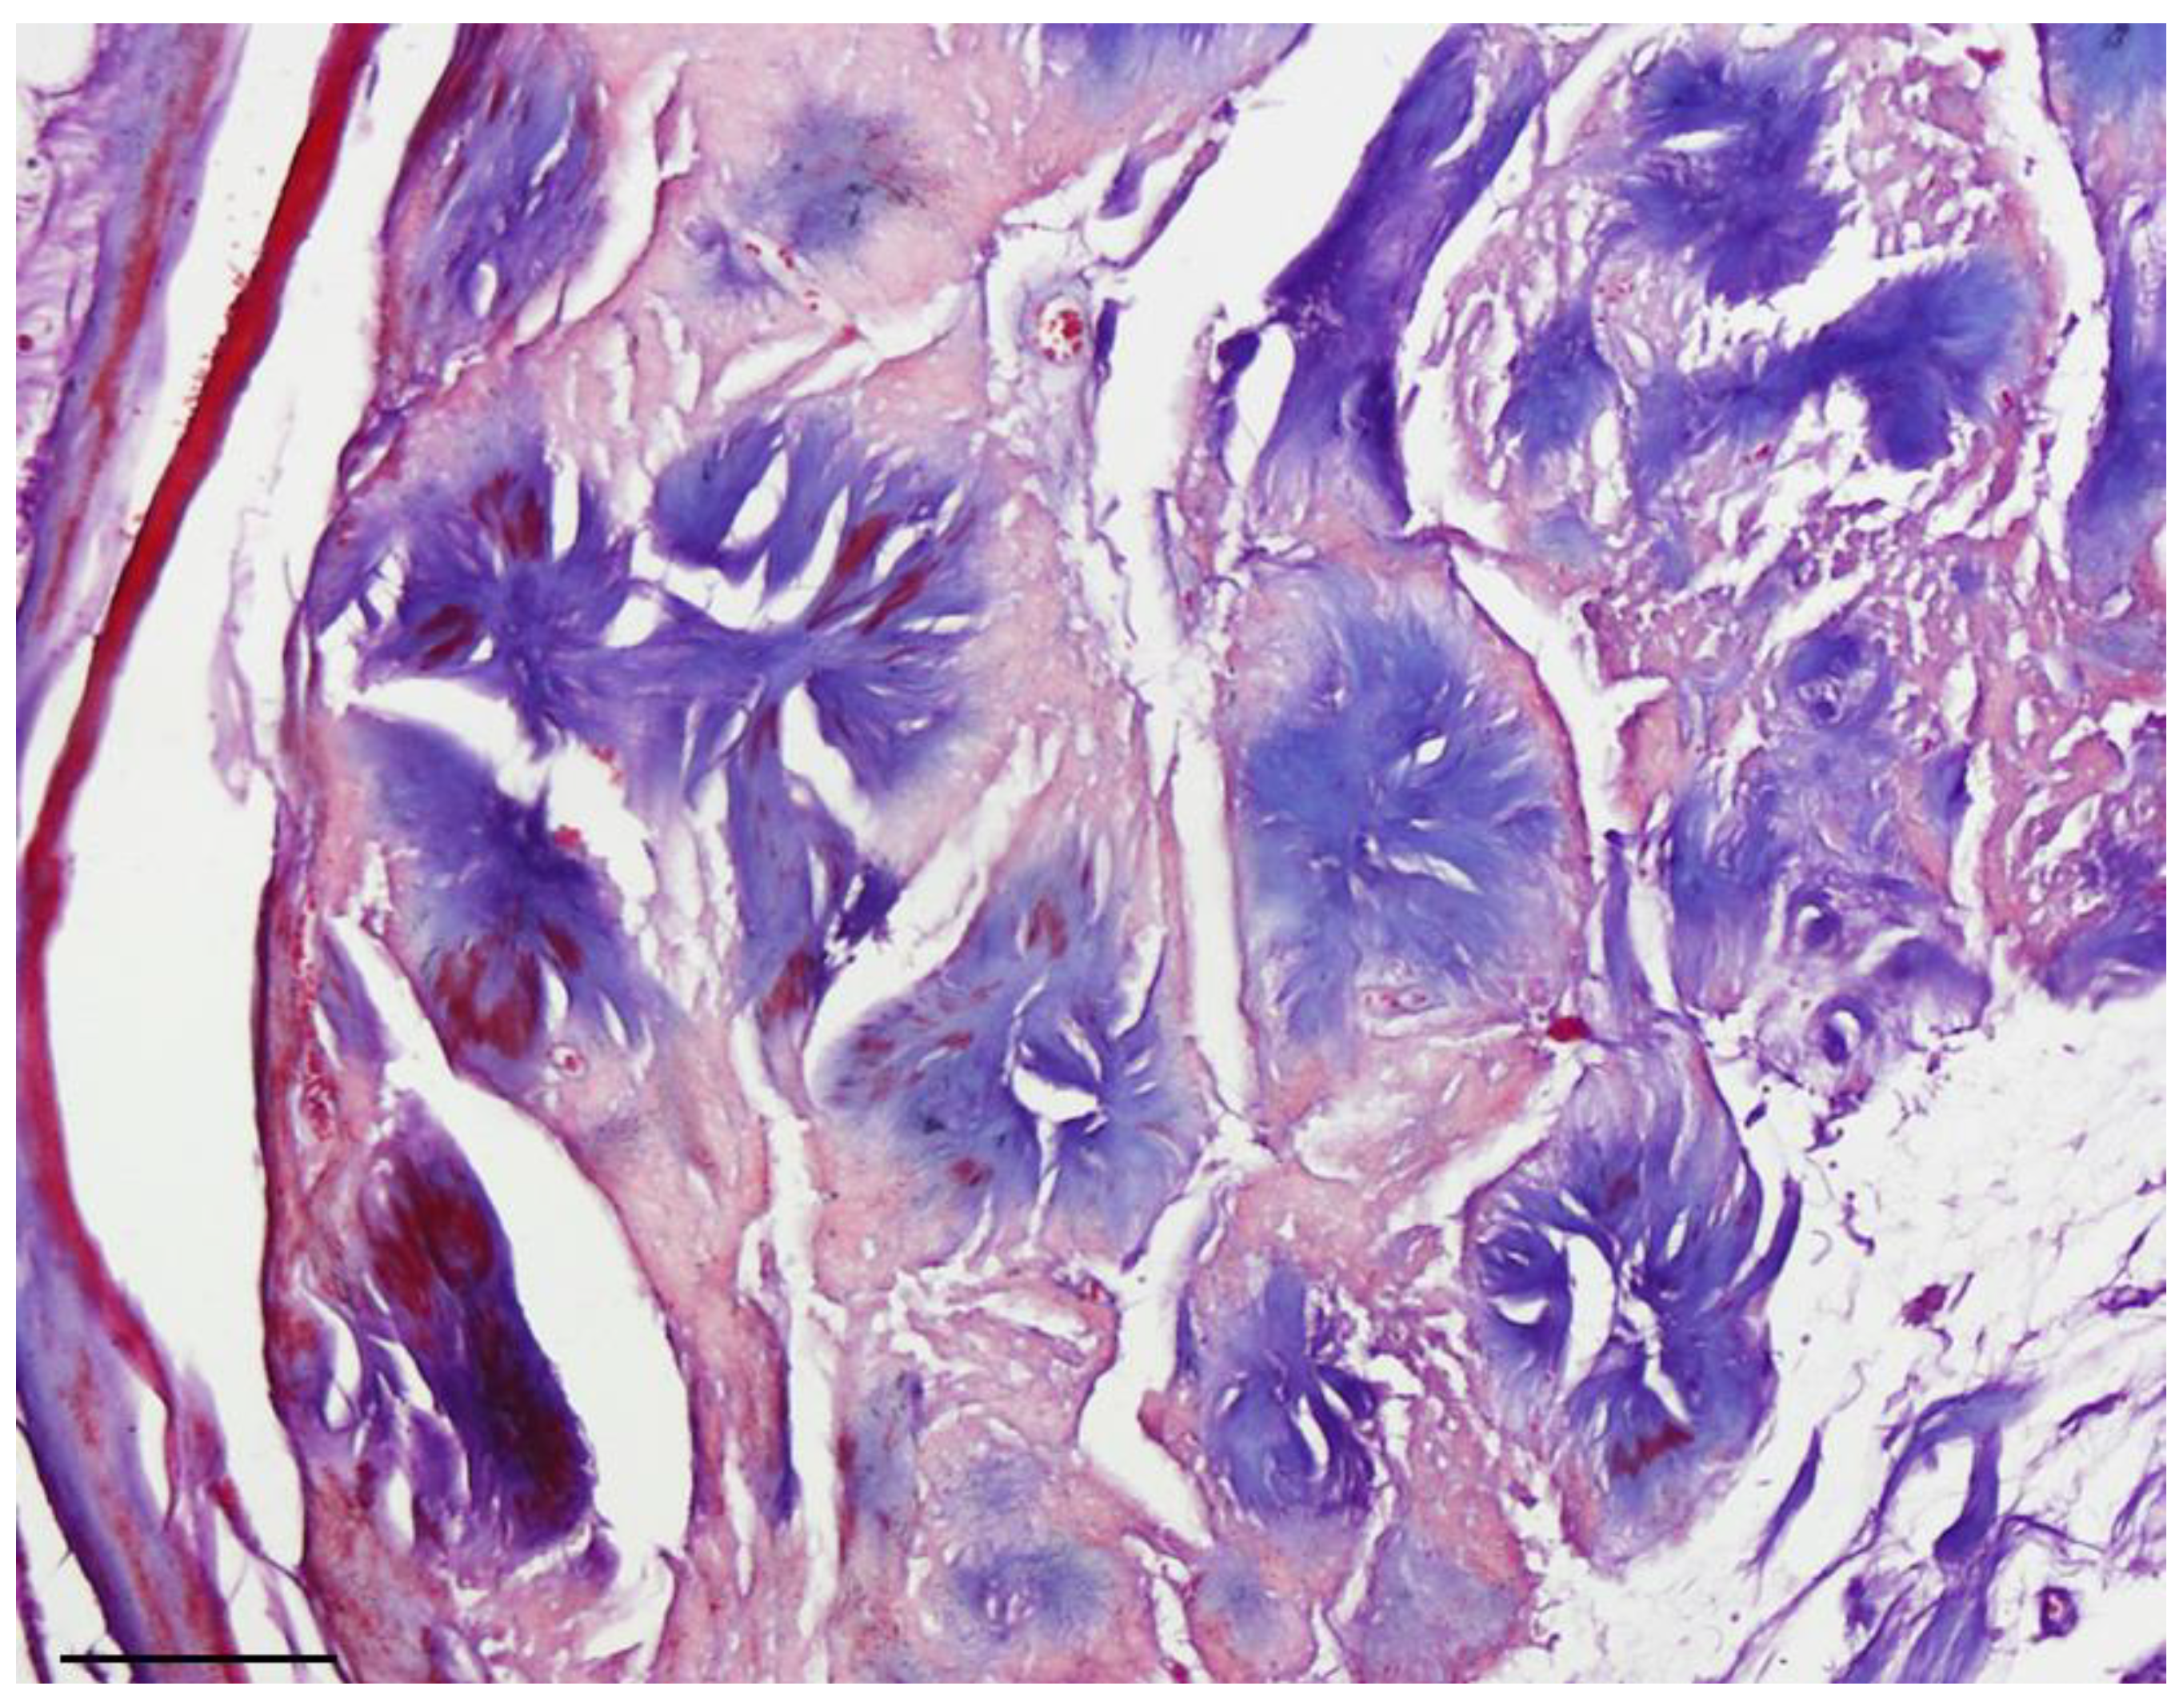

Masson’s trichrome staining confirmed that the central core of the rosettes was composed of collagen fibers. Subsequent immunohistochemical study revealed diffuse expression of S100 protein (as the most commonly used marker to detect tumoral cells) [6] in the tumoral cells, confirming the Schwann cell origin of the tumor (Figure 1 and Figure 2). Additionally, staining for the neural markers showed focal positive expression for Neuron Specific Enolase (NSE) and negative for synaptophysin which confirmed our diagnosis (Figure 3 and Figure 4).

Difference in the size of rosettes is considered an important histological criterion to distinguish neuroblastoma from neuroblastoma-like schwannoma [2,5]. In agreement with previously reported observations, rosettes in our neuroblastoma-like schwannoma case were trichrome positive [12].

Figure 2. Masson Trichrome, collagen core of rosettes stained blue (40× objective lens, scale bar = 50 μm).